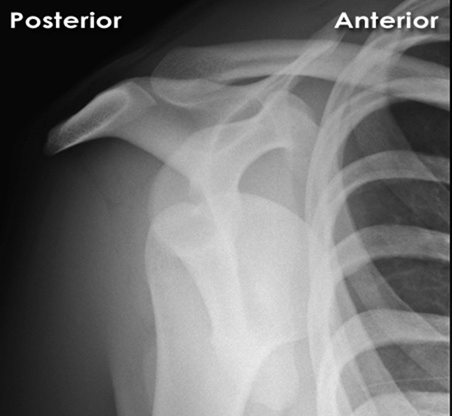

A 50-year-old patient presents with acute shoulder pain after a seizure. On examination, the arm is held in internal rotation, and the anterior shoulder appears flattened. External rotation is severely restricted. Which radiographic finding on an AP shoulder view is pathognomonic for a posterior shoulder dislocation?

Correct Answer: Trough line sign

The Trough line sign (or reverse Hill-Sachs lesion) is an impaction fracture on the anterior-medial aspect of the humeral head, often seen with posterior dislocations. The other options are incorrect: Hill-Sachs and Bankart lesions are typically associated with anterior dislocations. HAGL lesions are avulsions of the glenohumeral ligaments, often associated with anterior dislocations. Os acromiale is an anatomical variant.

What physical exam finding is MOST characteristic of a traumatic posterior shoulder dislocation?

Correct Answer: Restricted external rotation with the arm held in internal rotation

Explanation:

Traumatic posterior shoulder dislocations classically present with the arm held in adduction and internal rotation, with a hallmark inability to externally rotate the shoulder beyond neutral. The anterior shoulder may appear flattened, and the coracoid prominent. Option A is characteristic of anterior dislocation. Option B is incorrect. Option C is less specific than restricted external rotation. Option D is characteristic of anterior dislocation.